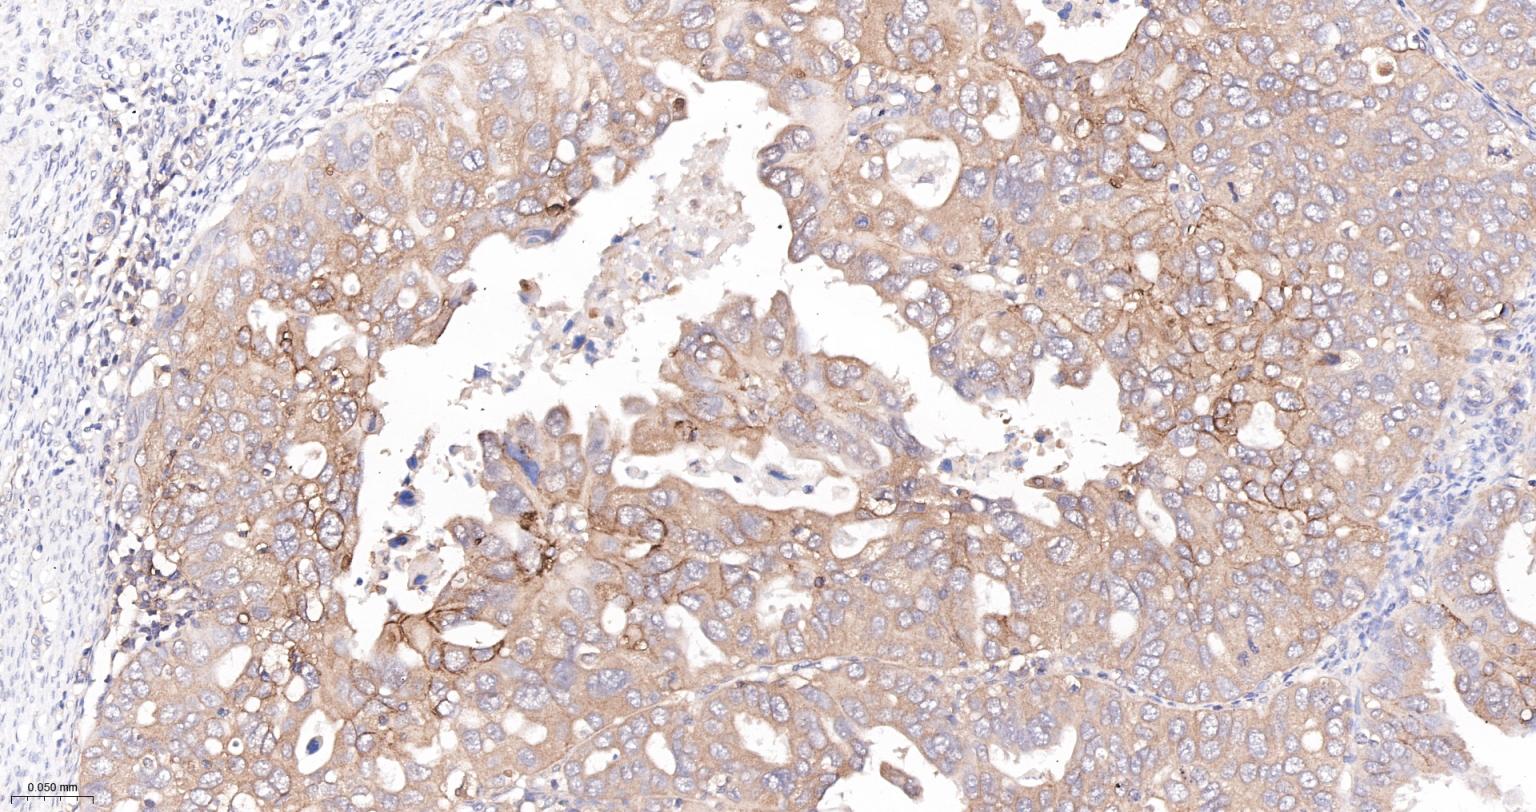

Paraformaldehyde-fixed, paraffin embedded Human Ovarian Cancer; Antigen retrieval by boiling in sodium citrate buffer (pH6.0) for 15 min; The section was incubated with TFRC Monoclonal Antibody, Unconjugated (bsm-54633R) at 1:400 overnight at 4°C, followed by conjugation to the bs-0295G-HRP and DAB (C-0010) staining.